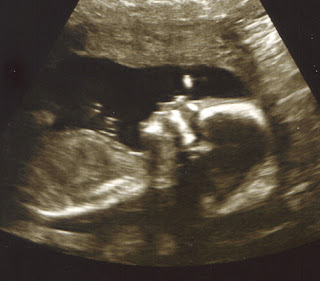

IT'S A BOY!

In case you can't tell what you're looking at in the above photo, picture that the baby has sat on a copying machine. His little bum cheeks are in the right corner of the photo, and his leg bone shows up bright white stretching out to the left of the photo. In the middle of the black area is his little manhood - no guessing, this is for sure a baby boy!

You're looking at the baby's head in the middle of the photo above, with the dark circles being the eye sockets. His little back is on the left of the picture.

This was my favorite picture from the ones given to us that day. While it's hard to see here from the scan, the baby is laying ever so peacefully almost on his stomach (how the rest of my boys - including Daddy - like to sleep). His little face is so dear in this picture!

I thought the baby looked a little alien-esque in this photo, but you can really see his skull, nose, lips and jawline.

The baby loves to have his hands by his face. In this photo, you can really see his arm and hand. Every time the tech wanted to see something, our little guy would put his hands right where she wanted to scan. He would also 'run away' as she put it. But, they got what they needed.